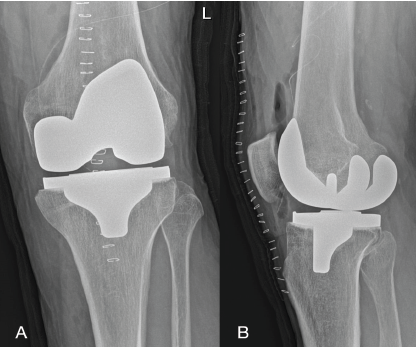

An Unusual Presentation of Delayed Hemarthrosis Following Total Knee Arthroplasty: A Case Report

Rudra Prabhu , Sneha Pimpalnerkar , Ashvin Pimpalnerkar , Vijay Gudla , Arul Ganeshan

………………………………p.111-115